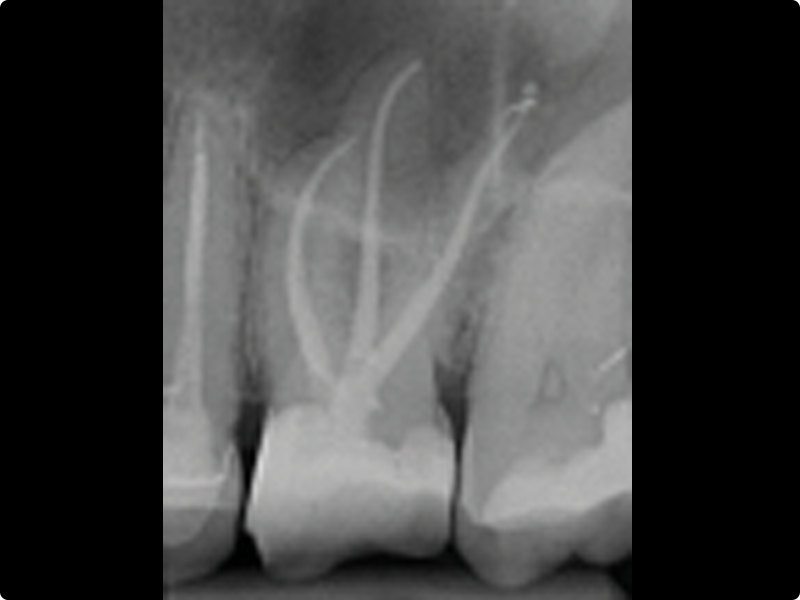

Through an essential theoretical session and an intensive practical workshop on extracted teeth, participants will experience canal shaping using traditional and martensitic instruments, both in continuous rotation and reciprocation, while exploring the advantages of bioceramic sealers. The course also covers canal obturation techniques and predictable retreatment procedures based on the latest clinical standards.

• Canal shaping: general principles

• Scouting, glide path, preflare

• Continuous rotation and reciprocation

• Management of calcified canals

• Working length

• Apical gauging and refinement

• Mechanical shaping of the canal body in continuous rotation and reciprocation on extracted teeth with access cavities already prepared by the participant (ideally at least 3 single-rooted and 3 multi-rooted teeth, both upper and lower, with access cavities prepared)

• Manual scouting and achievement of the correct working length

• Glide path and mechanical preflare

• Shaping using rotary and reciprocating systems